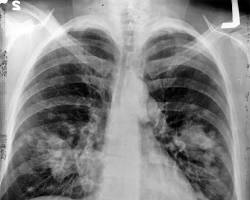

• Kanser: Sigara, akciğer kanseri, gırtlak kanseri, ağız kanseri, yemek borusu kanseri, pankreas kanseri, mesane kanseri ve lösemi dahil olmak üzere birçok kanser türünün riskini artırır.

• Akciğer hastalığı: Sigara, bronşit, astım ve amfizem gibi akciğer hastalıklarının riskini artırır.

• Astım

• Kronik obstrüktif akciğer hastalığı (KOAH): Sigara, KOAH, solunum güçlüğü ve ölüme neden olabilen ciddi bir akciğer hastalığı riskini artırır.

• KOAH